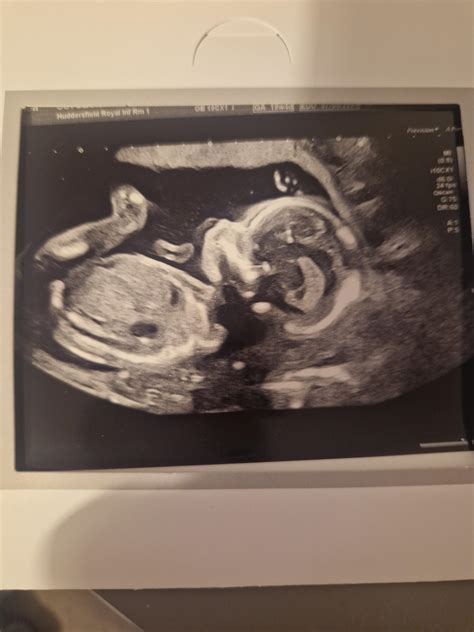

The 20-week anatomy scan is a routine ultrasound offered by the NHS to pregnant women, typically performed between 18 and 21 weeks of gestation. Its primary goal is to assess the physical development of the fetus and identify any major congenital anomalies. During the scan, a trained sonographer will meticulously examine various organs and body parts, including the brain, heart, spine, kidneys, and limbs. They’ll also check the position of the placenta and measure the amniotic fluid levels. This comprehensive evaluation aims to provide parents with as much information as possible about their baby’s health, allowing for timely intervention and informed decision-making if necessary.

The importance of the 20-week scan cannot be overstated. It serves as a crucial screening tool, detecting a wide range of conditions, from structural abnormalities like spina bifida and cleft palate to heart defects and kidney problems. Early detection allows for better management of these conditions, potentially improving outcomes for the baby after birth. In some cases, the scan may reveal a minor issue that requires no intervention at all, providing reassurance to expectant parents. However, if a more serious problem is suspected, the scan results will prompt further investigations and consultations with specialists. Remember, the 20-week scan is just one piece of the puzzle. It’s designed to identify potential risks, but it’s not always definitive. Further tests and expert opinions are often needed to confirm a diagnosis and determine the best course of action. So, try to stay calm and gather all the necessary information before jumping to conclusions.